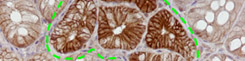

El diari EL PUNT publica una entrevista realitzada a Eduard Batlle, investigador de l’IRB Barcelona. L’entrevista recull les opinions del científic sobre el premi Banc Sabadell, que recentment ha rebut, y els últims avenços sobre el tractament dels tumors.